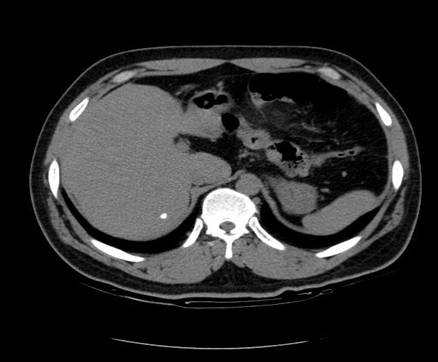

以下是引用zsl6918在2007-6-22 21:08:00的发言:[br]病史较长,反复发作,基本排除恶性病变,腹部定位像可见是小肠梗阻征象,原因无非是肠源性,血管性和神经性的,肠源性的在排除占位后应想到 肠旋转不良的可能,血管性的应想到肠系膜血管的栓塞,神经性的要想到植物神经功能紊乱的可能,本病例应该强化检查帮助诊断,个人感觉旋转不良可能性大。

以下是引用青莲居士在2007-6-24 12:27:00的发言:[br]肠梗阻[br]肝内胆管结石